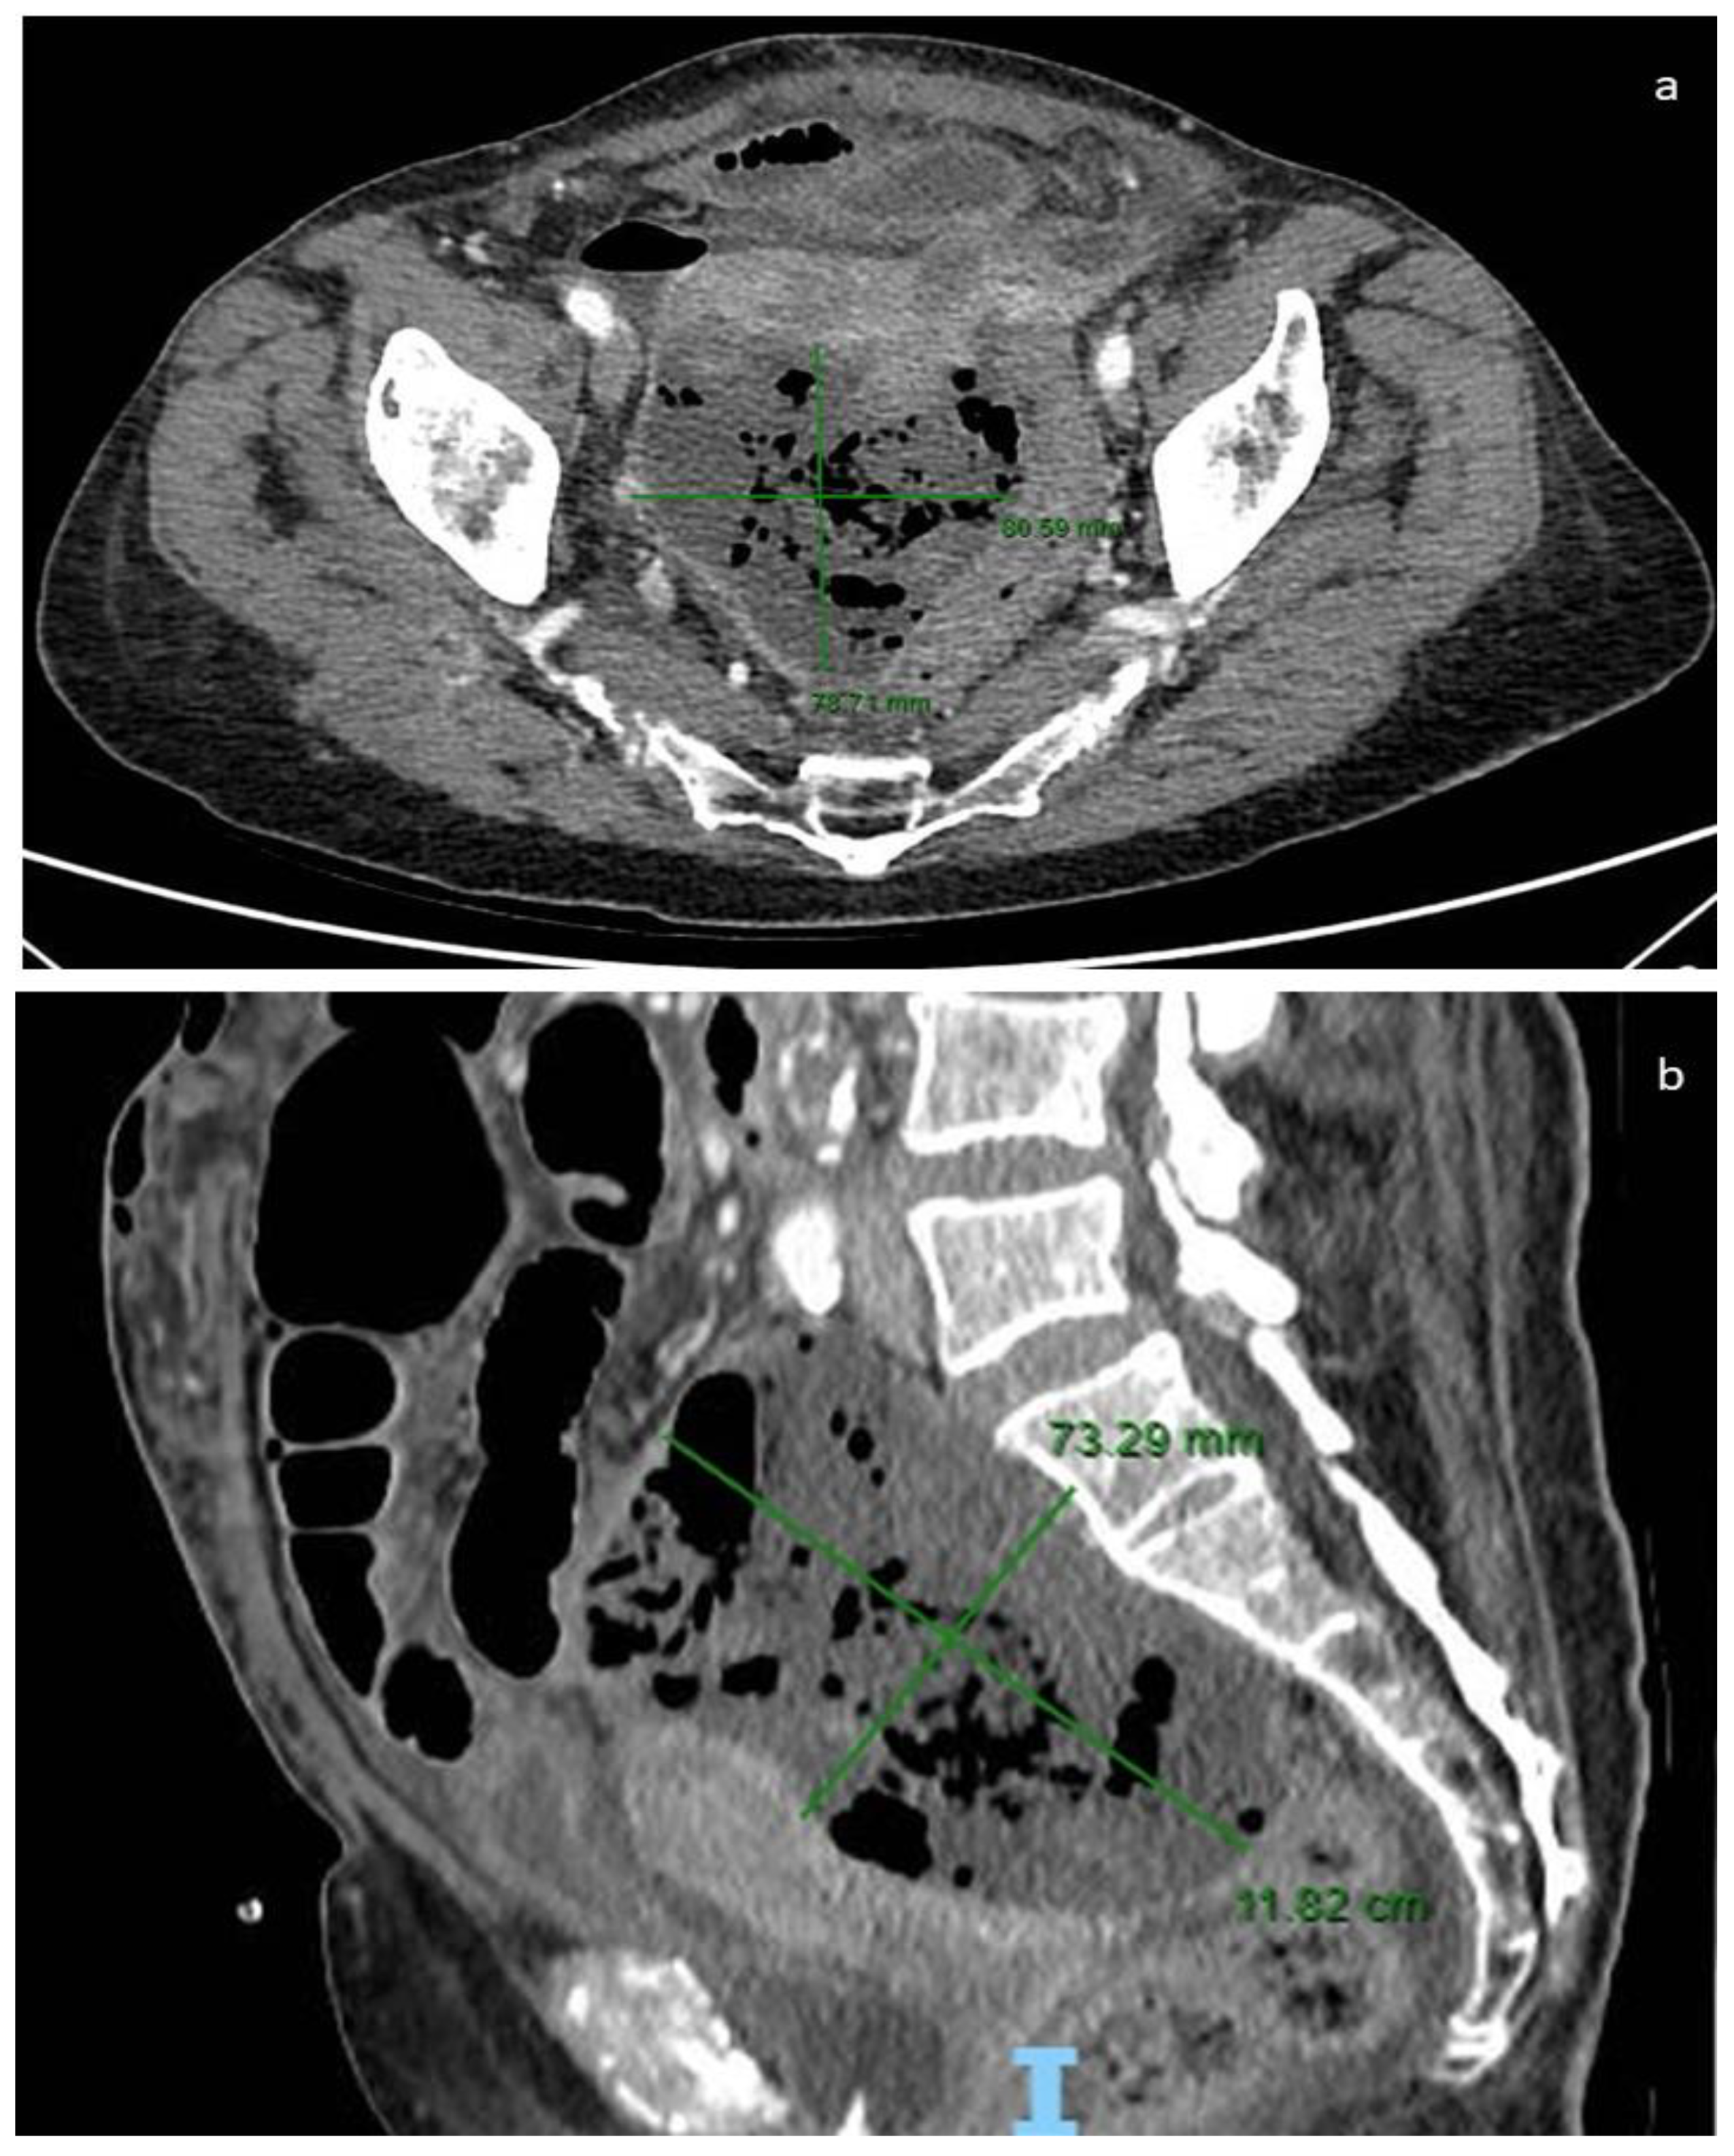

Differently from epithelial ovarian cancer (EOC), GISTs showed normal or slightly increased blood Ca-125 and Ca-19.9. Particularly, Group 2 patients showed increased serum Ca-125 and Ca-19.9 values more frequently than Group 1 cases (71% vs. 40% and 50% vs. 7%, respectively). In the latter cases, serological markers may cause diagnostic misinterpretation with gynecological cancers, particularly those arising from the adnexa. Not only the clinical diagnosis can be challenging in differentiating GISTs from adnexal masses but sometimes also radiologic investigation such as CT or MRI can raise problems in interpretation. CT is considered the best imaging method for diagnosing and describing tumors and for evaluating their extent and metastatic disease (Figure 2).

CT is useful for preoperatory diagnosis (CT-guided biopsy), to evaluate the full thickness of the small intestine and mesentery, and to determine the response to adjuvant therapy [81]. The density of GISTs on non-contrast CT is similar to that of the muscles and its enhancement varies. Intratumoral gas suggesting communication with the gastrointestinal lumen, calcifications, and intratumoral hemorrhage are easily identified. CT enterography may be useful for identifying small GISTs in the small bowel of patients with suspected small bowel bleeding [82]. Moreover, CT may define the size of GISTs, which correlate to stage and prognostic risk classes. GISTs larger than 10 cm were more frequently associated with peritoneal or distant metastasis, increased mortality rates, or high-grade histology. Morphologically, these GISTs frequently showed irregular growth margins with invasion to adjacent organs [83,84] (Figure 3); however, CT may fail to detect small ovarian metastases [52].

Figure 3. Our case: CT image with measurements: axial plane (a) and sagittal plane (b).